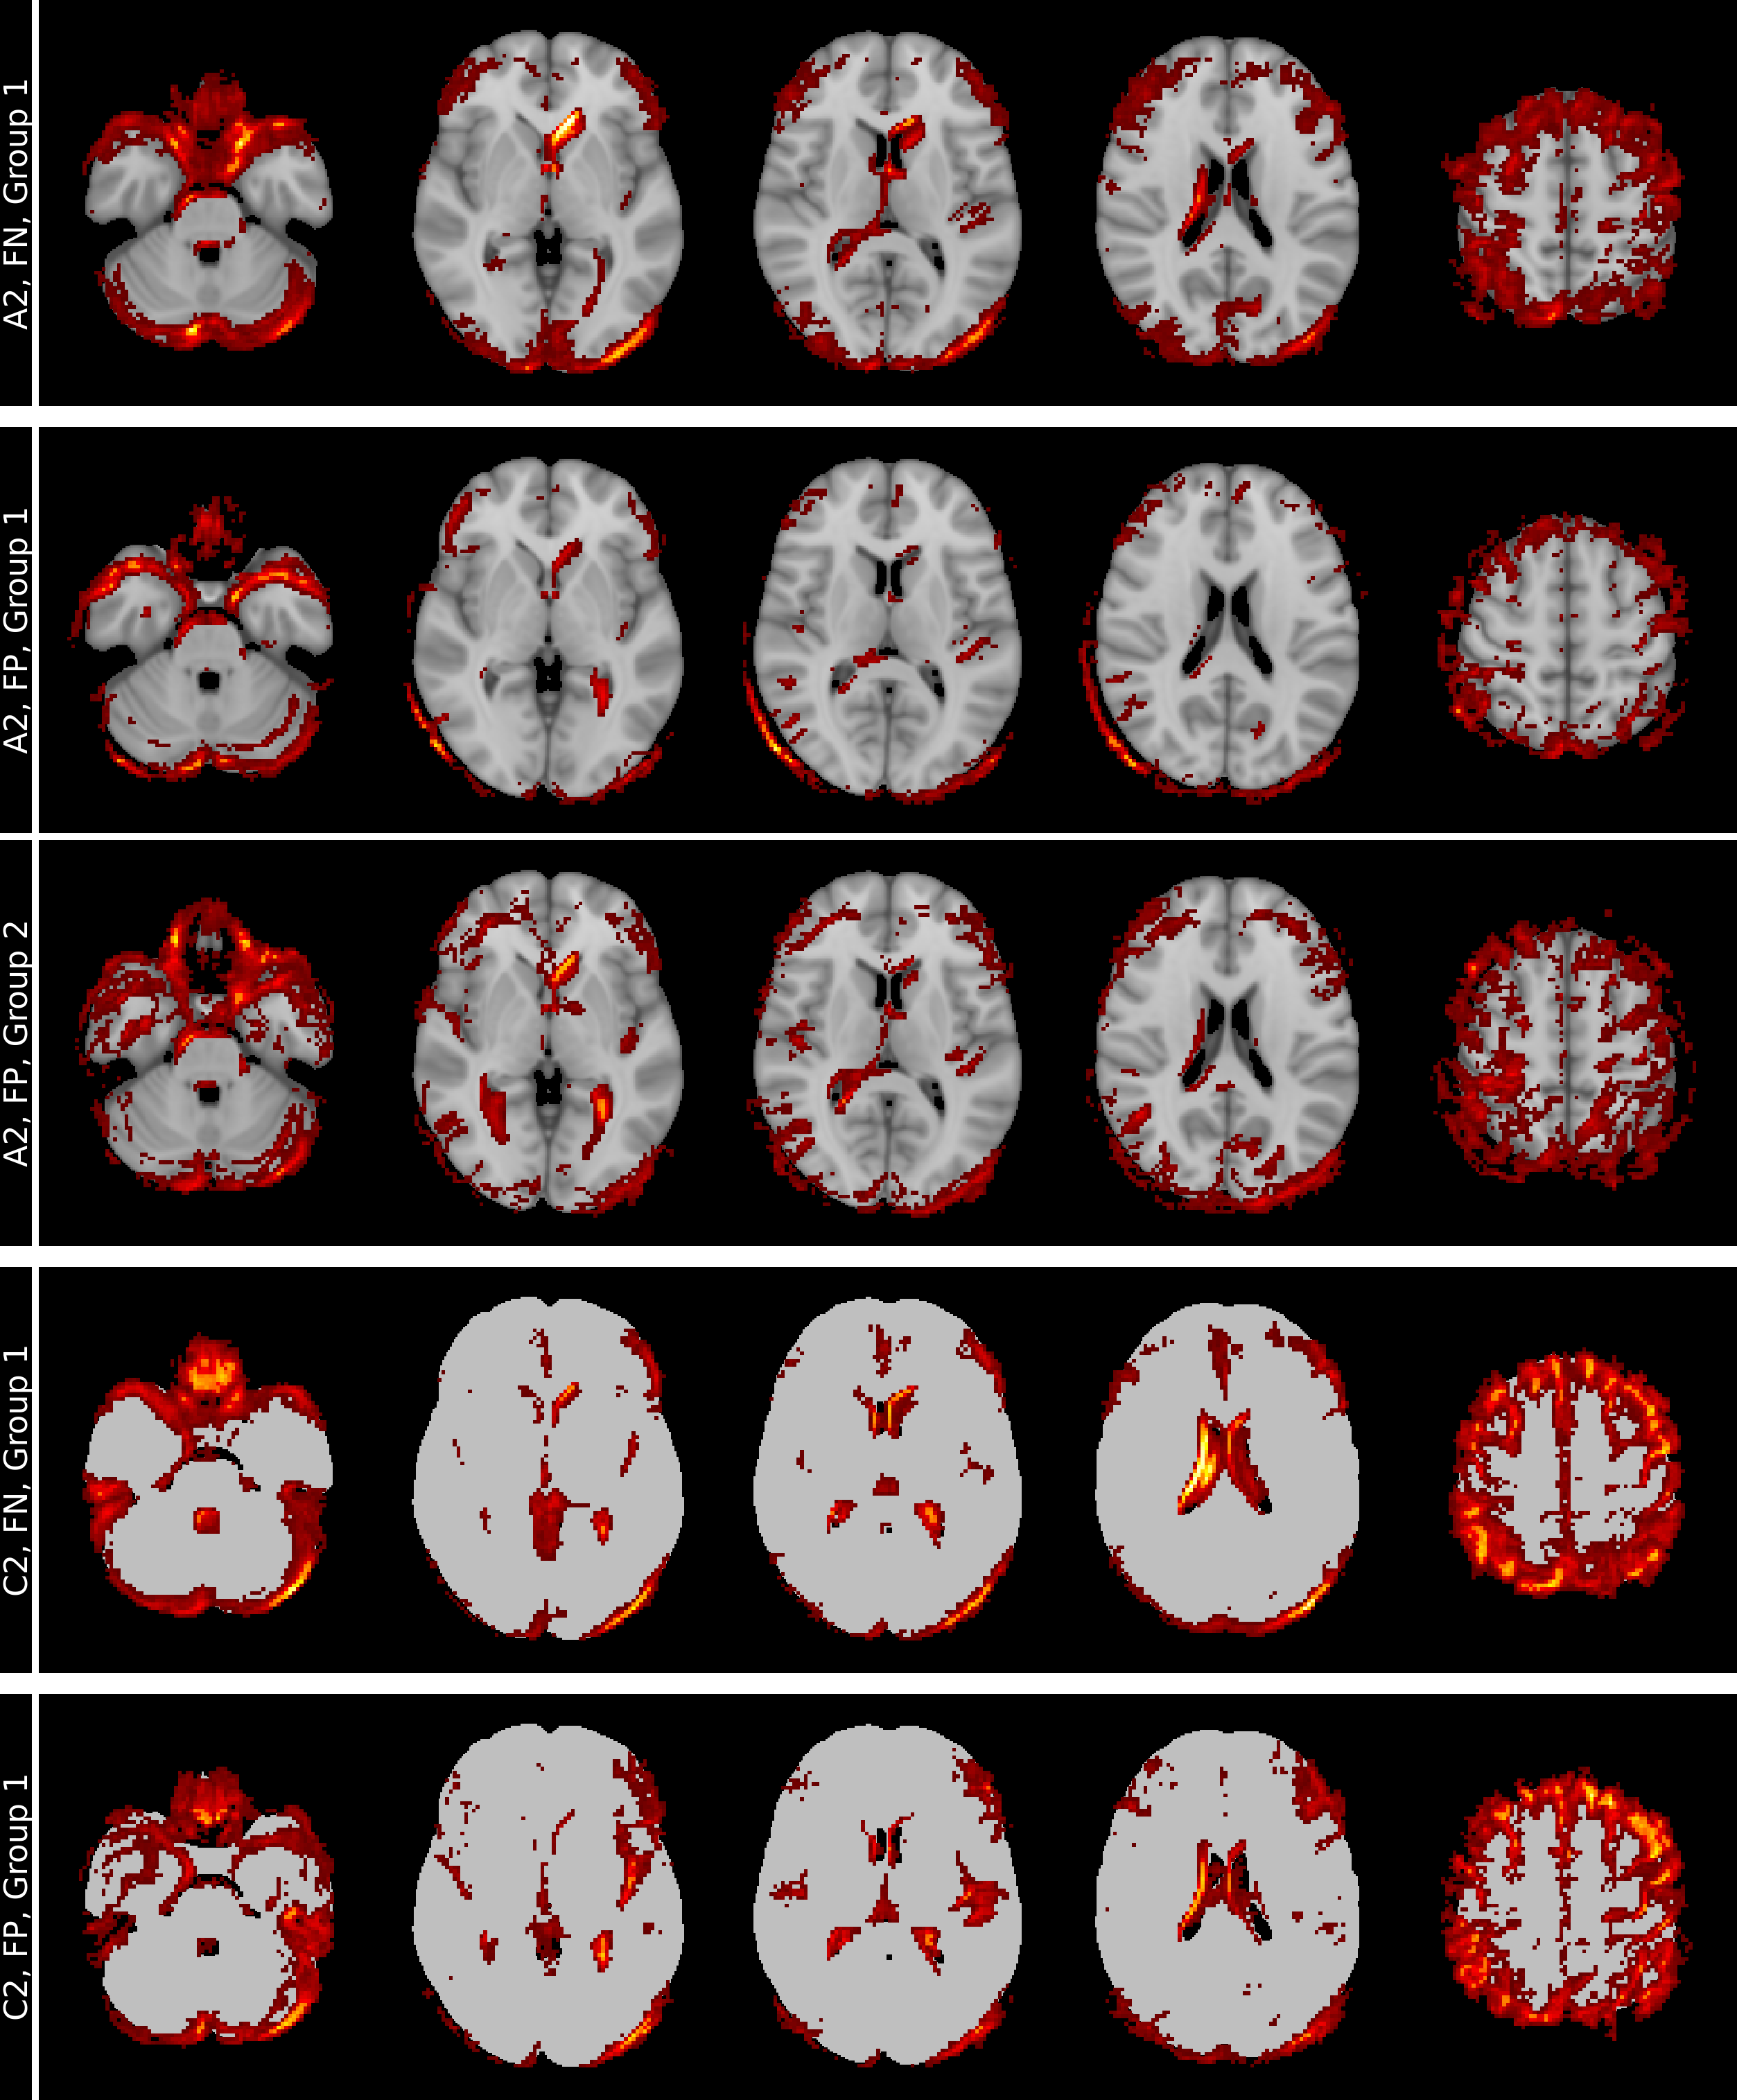

Raw T1w images were reoriented to standard space using FSL-REORIENT2STD [20], cropped to a 160×240×256160\times 240\times 256 matrix size, bias field corrected using N4 [44], and non-linearly registered to the MNI152 template via FSL-FNIRT [20]. Intensity values were normalized to the white matter peak of the brain tissue histogram (196 bins). The outputs of this preprocessing pipeline are referred to as “aligned” images. Individual brain masks were generated in native image space using SIENAX from FSL [39] and warped to the aligned images to create the “skull-stripped” images. Binary masks preserving shape information were derived using manually selected thresholds of 13.75%, 27.5%, and 41.25% of the white matter peak of the brain tissue histogram and the aligned images. These binary masks were also combined with skull-stripped preprocessing, resulting in eight total setups, as illustrated in Figure 1. Supplementary Figure 5 in Supplementary Material 1 illustrates that thresholds were selected to preserve meaningful atrophy patterns by comparing residual voxels with individual brain masks.

Refer to caption

Figure 1: Input image setups: Left column with (A1) aligned T1w MRI, identical binarized T1w images with the manually selected threshold levels (B1) 13.75%, (C1) 27.50% (C1) and (D1) 41.25%, and in the right column the corresponding skull-stripped versions (A2, B2, C2, D2).

We investigated three binarization levels, each aligned with the white matter intensity peak of the image, as depicted in Figure 1. These levels, although chosen arbitrarily, retained differing proportions of anatomical structures, capturing distinct aspects of atrophy, including ventricular enlargement, hippocampal shrinking and cerebellum morphology. As CNNs seem to focus on high-contrast regions [15, 31], these binarization levels allowed us to systematically dissect how different volumetric and structural features influenced model predictions.